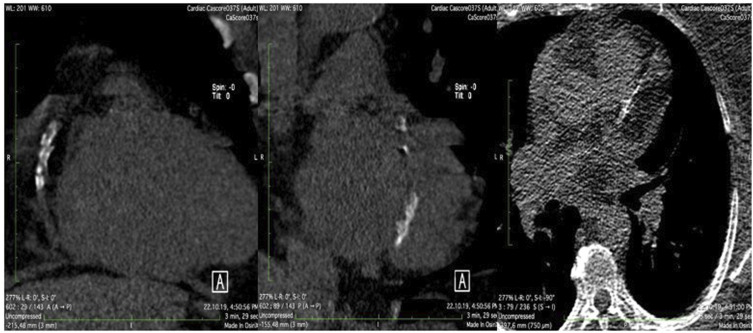

Objective: Long-standing diabetes mellitus is often associated with cardiovascular complications. We aimed to evaluate the presence, extent and composition of subclinical atherosclerotic plaques in coronary arteries by Computed Tomography in patients with newly diagnosed type 2 diabetes mellitus (NDT2DM), and to identify the predictors.

Methods: In this study 101 consecutive patients with NDT2DM were included. Patients were categorized into five groups based on their Coronary Artery Calcium Score (CACS) ranging from 0, 0-10, 11-100, 101-400 to >400. All parameters were compared across these groups.

Results: The average patient age was 54.4 ± 11.6 years and 48 (47.5%) were females. Eight (7.9%) patients had CACS 0, 6.9% CACS 1-10, 42.6% CACS 11-100, 22.8% CACS 101-400 and 19.8% had CACS >400. Multiple regression analysis for the general data identified weight (p = .04) and systolic blood pressure (p = .033) as independent predictors for CACS.

Conclusions: Asymptomatic patients with NDT2DM in more than 90% of cases may present with calcified atherosclerotic plaques and this may be predicted by: patient weight and the level of systolic arterial pressure. Our study emphasizes the need for comprehensive care and early prevention of cardiovascular complications in individuals with NDT2DM.